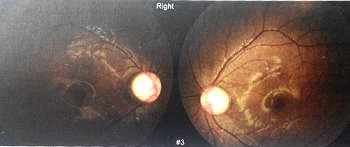

配镜三个月后,洪洪告诉我,他坐在第一排都看不见黑板上的字。这时老师也打电话来说,我家小孩上课总是开小差。我一听心想:看不见黑板肯定上课要分心。于是二零一二年五月,我们再次来到华西医院進行检查,一检查吓一跳,医生告诉我:“你家小孩的眼睛验光,三百度也只能看到零点八,二百度也是零点八,度数上不去。你带他做一个全面的检查。”于是我们让医生做了全面的检查,下面这些就是当时做眼部OCT时照出来的图片:

OD OCT图

视盘图

最后经过医院医生的确诊,得出的结论是双眼发育性青光眼。原来,洪洪歪着脑袋斜着看是因为眼底正前方可能被强光灼伤(见黄斑区),所以只能歪着脑袋才能正确聚焦。